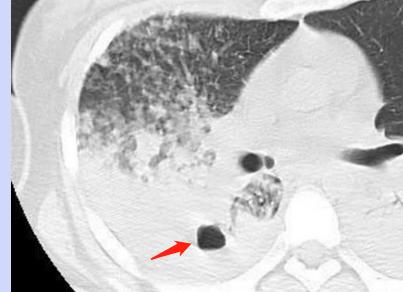

3.肺组织实变:

结核杆菌感染可以引起某些肺叶、肺段的炎症性实变,肺内空气消失:

结核杆菌感染引起左下肺干酪性肺炎